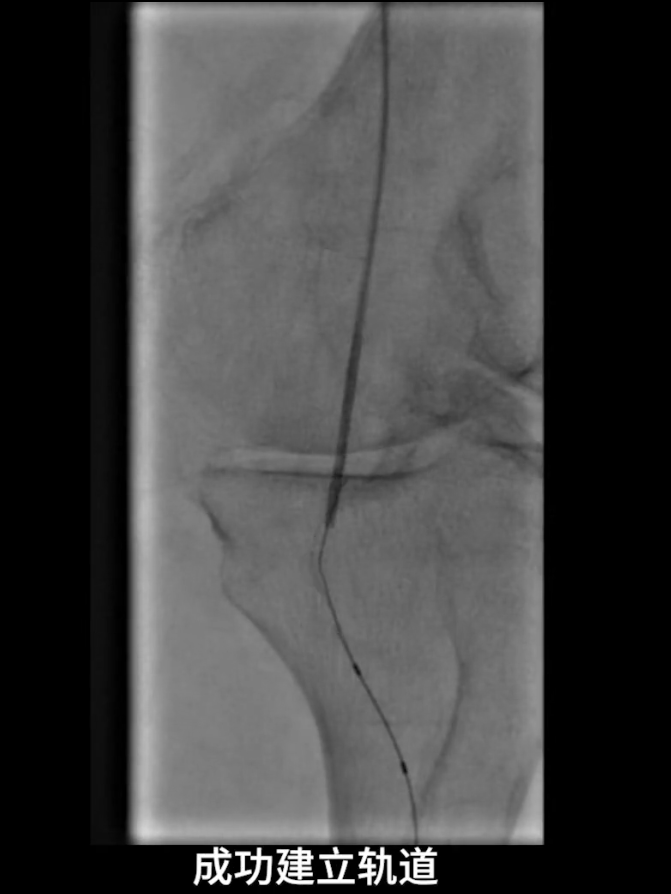

首先尝试顺行通过股浅动脉闭塞段,导丝进入内膜下,开通失败;遂改为逆穿策略,以支撑导管配合V18导丝逆行通过股浅动脉闭塞段,最终与近端股浅动脉真腔成功对接,建立安全操作轨道。